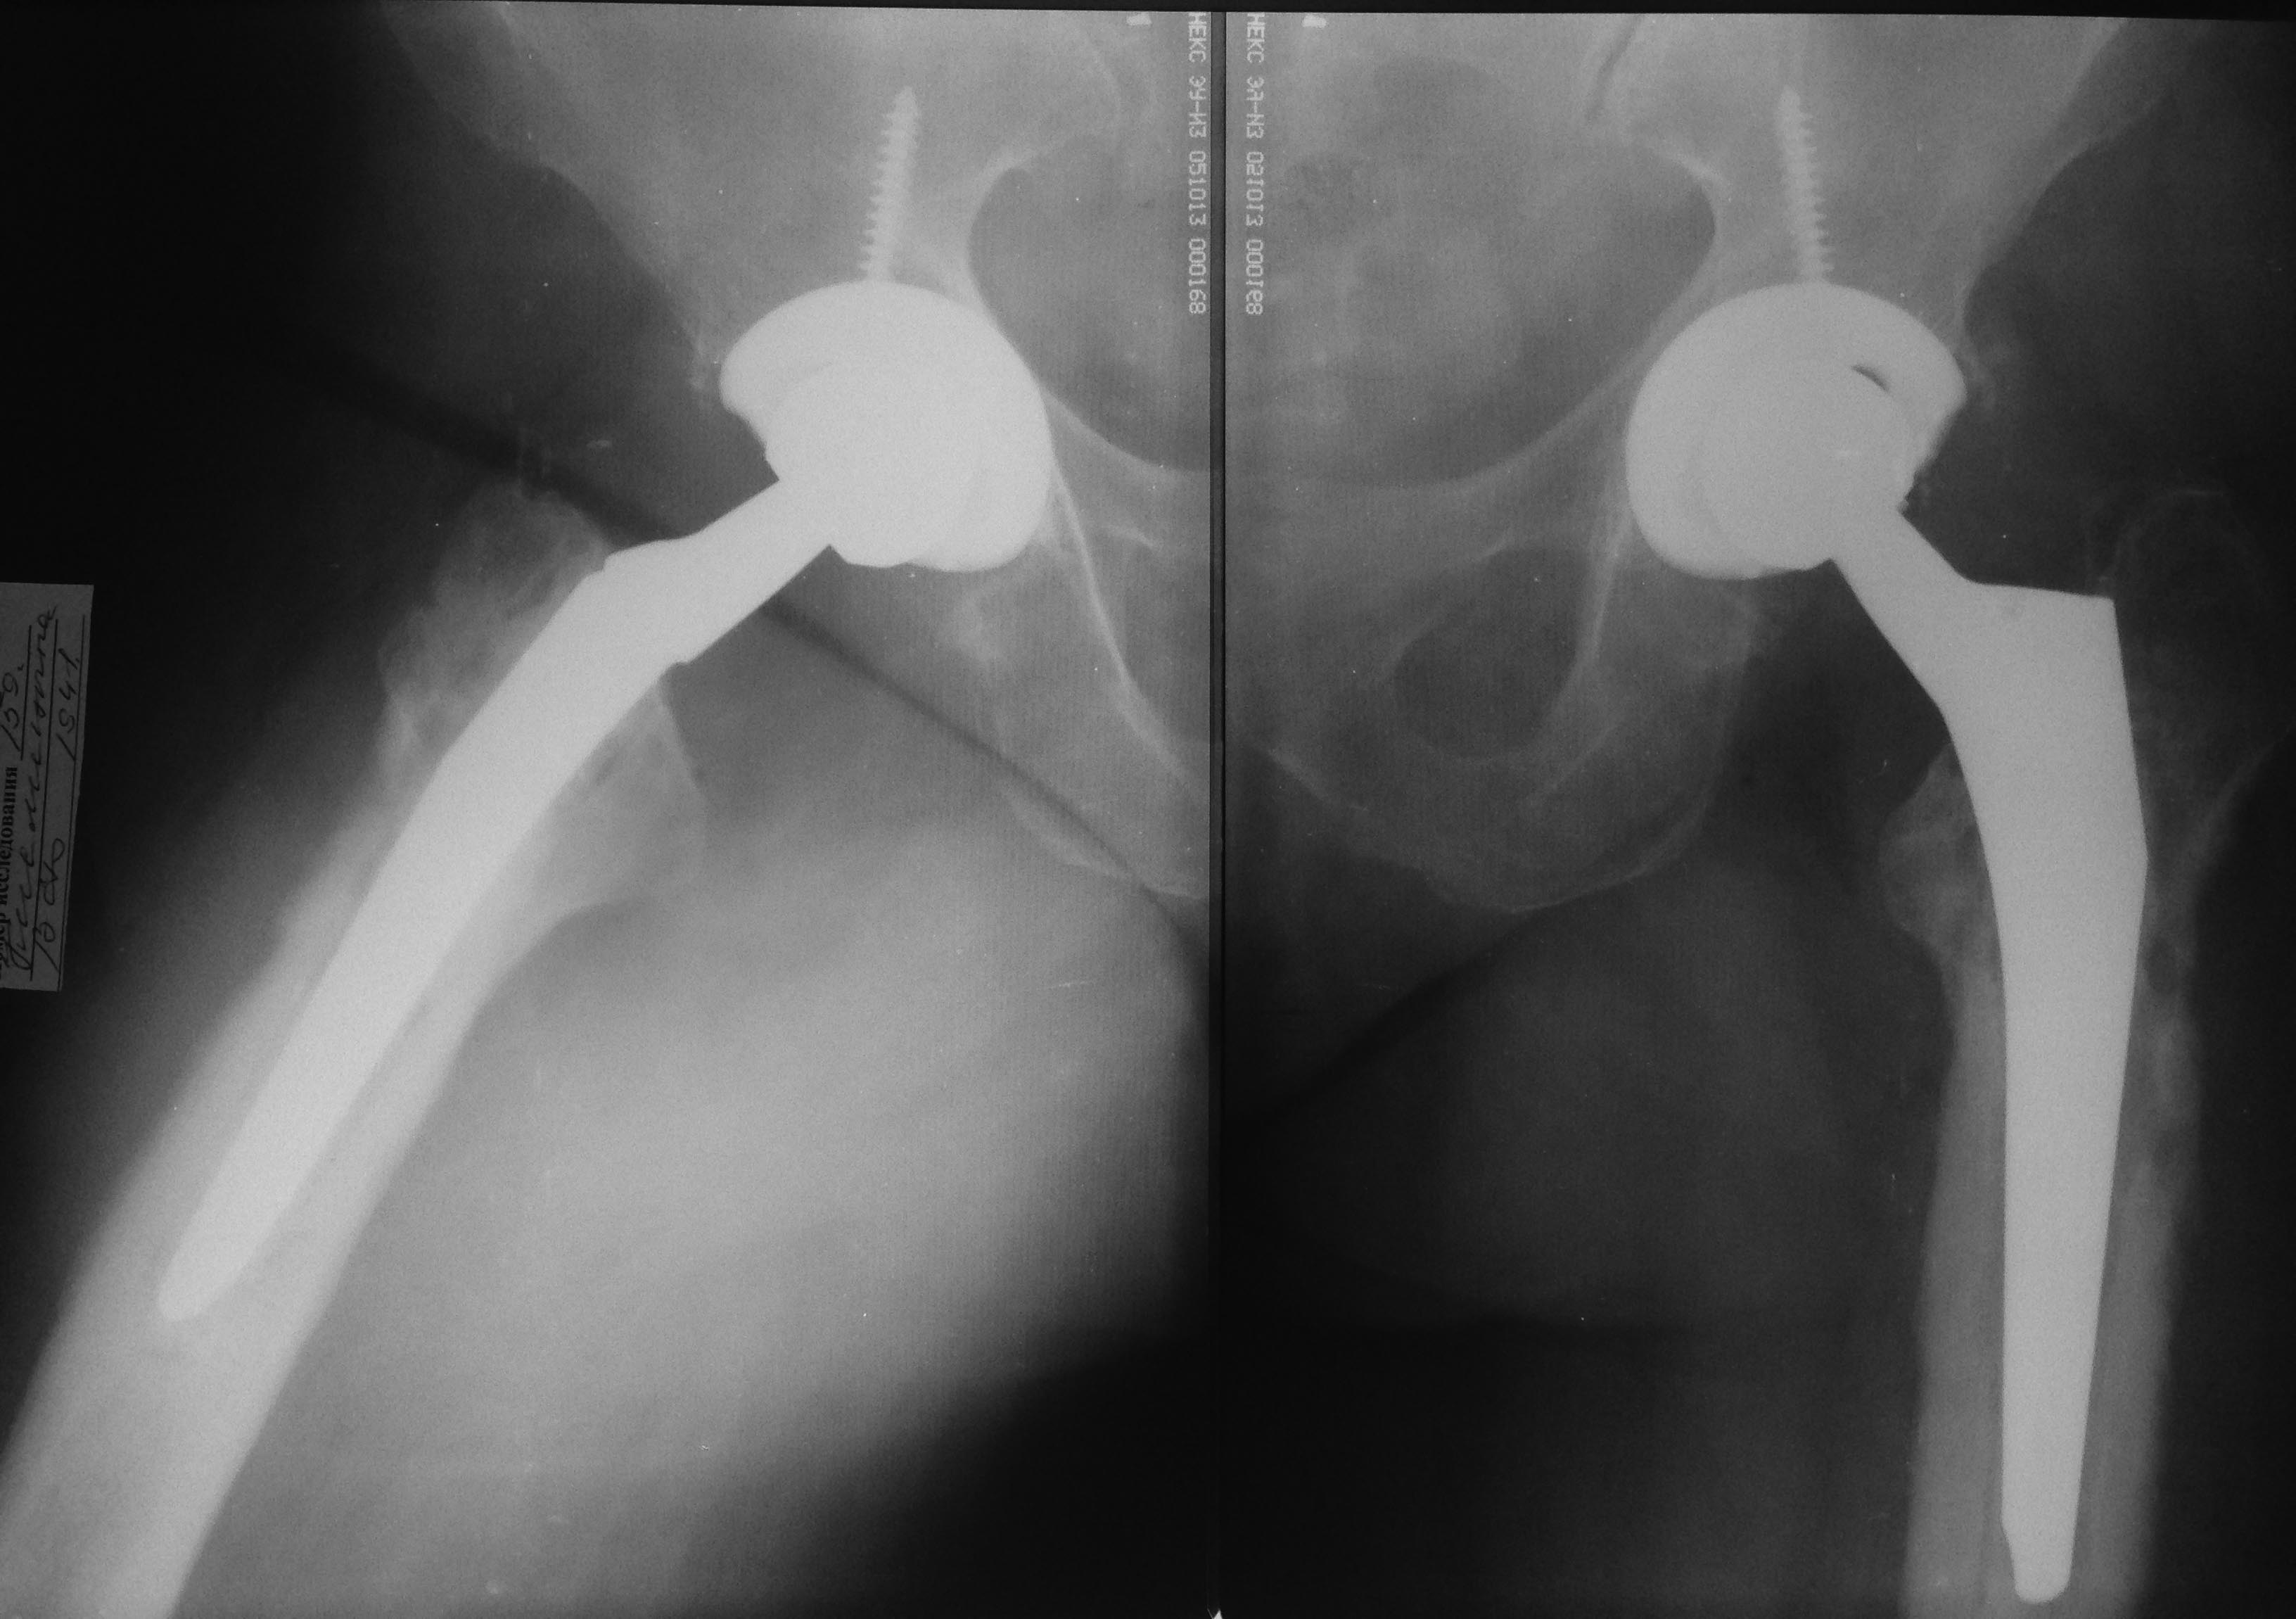

Собственно снимок

Чашка Zimmer Trilogy, ножка Zimmer стандартная Мюллера, цемент synicem 3G с гентамицином

Николай! Сделайте анализы крови на воспаление. Возможно это инфекция. По снимку не похоже на нестабильность элементов. Проксимальный отдел не разрушен, но есть явления локального пороза. Скорее причина его в концентрации нагрузок на дистальный отдел ножки ЭП. Есть выражение у В.Даниляка: увидел пороз ПОБК, сделай ревизию, не жди расшатывания. Думаю, что возможная причина в неврологии. Нужно дообследовать. АИФ

Бедренный и вертужный компоненты клинически стабильны.

Вы имеете ввиду стресс-шелдинг синдром?

вертлужный компонет, как минимум, "вероятно нестабильный", резорбция есть, явных признаков изменения положения нет. Ни о шилдинге ни о байпасе пока речь не идет